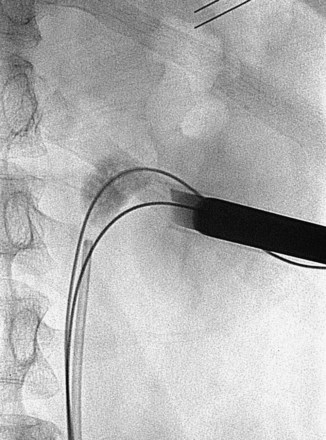

The “ultimate” retrograde assistance to percutaneous access into the upper urinary tract collecting system is the retrograde approach to percutaneous access. Although the antegrade approach is much more commonly performed, a retrograde approach may be selected when the surgeon has limited experience with antegrade percutaneous renal puncture or in situations in which there might be a technical advantage to the retrograde approach such as morbid obesity or a hypermobile or abnormally situated kidney (Mokulis and Peretsman, 1997). The Lawson Retrograde Nephrostomy Wire Puncture Set (Cook Urological; Spencer, IN) is the device commercially available for this use. After retrograde placement of a guidewire into the renal pelvis, pass the 7-Fr Torcon catheter—which is actively deflectable from 0 to 140 degrees (Fig. 47–14A)—over the guidewire and into the desired calyx. Insert the 3-Fr polytetrafluoroethylene (PTFE) sheath containing the 0.017-inch stainless steel puncture wire through the Torcon catheter. Advance the puncture wire through the kidney and body wall under fluoroscopic control, withdrawing and repositioning it if any obstacles such as a rib are encountered (Fig. 47–14B). Make a small skin incision and grasp the wire externally. Use the fascial dilators in an antegrade fashion until the Torcon catheter can be advanced through the tract. Once the end of the catheter exits the skin, exchange the puncture wire for a standard 0.035 inch guidewire, thus attaining through-and-through access.

The antegrade approach to percutaneous access into the upper urinary tract collecting system is the standard. It affords the most control of the skin entry site and can be guided by ureteroscopy or a variety of imaging modalities.